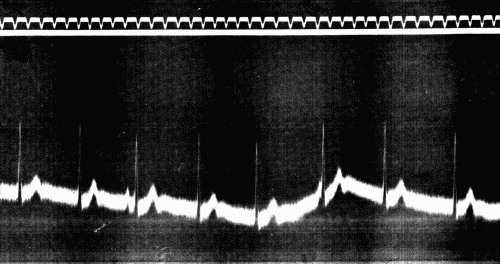

29. Tracing of auscultatory phenomena94

30. Tracings of auscultatory phenomena95

31. Clinical determination of diastolic pressure fast drum96

32. Clinical determination of diastolic pressure slow drum96